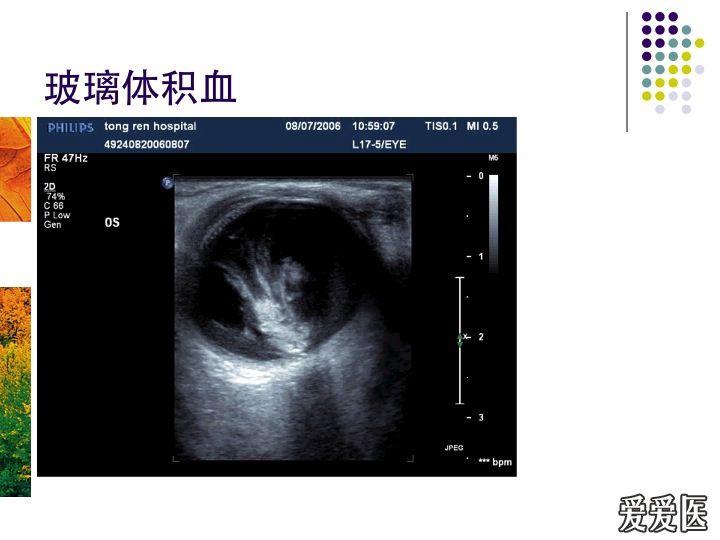

- 玻璃体积血图片尺寸1080x731

- 玻璃体积血 - 超声医学讨论版 - 爱爱医医学论坛图片尺寸720x540